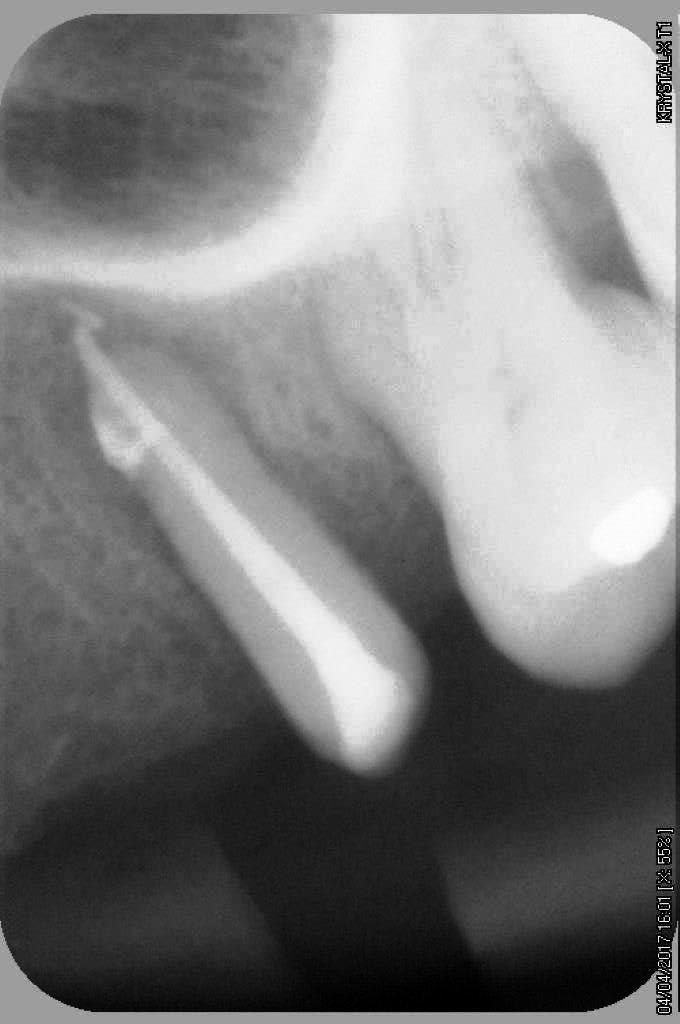

petit cas sympa ancien bridge très mobile....plutôt que d'extraire 25, j'ai déposé la couronne, retraité la dent stabilisation pendant deux mois puis séance d'ostéotension et ce jour pose de deux axioms PX 34120 après expansion...

non, uniquement travail par voie crestale, très légère fêlure niveau 23, mais sans conséquence